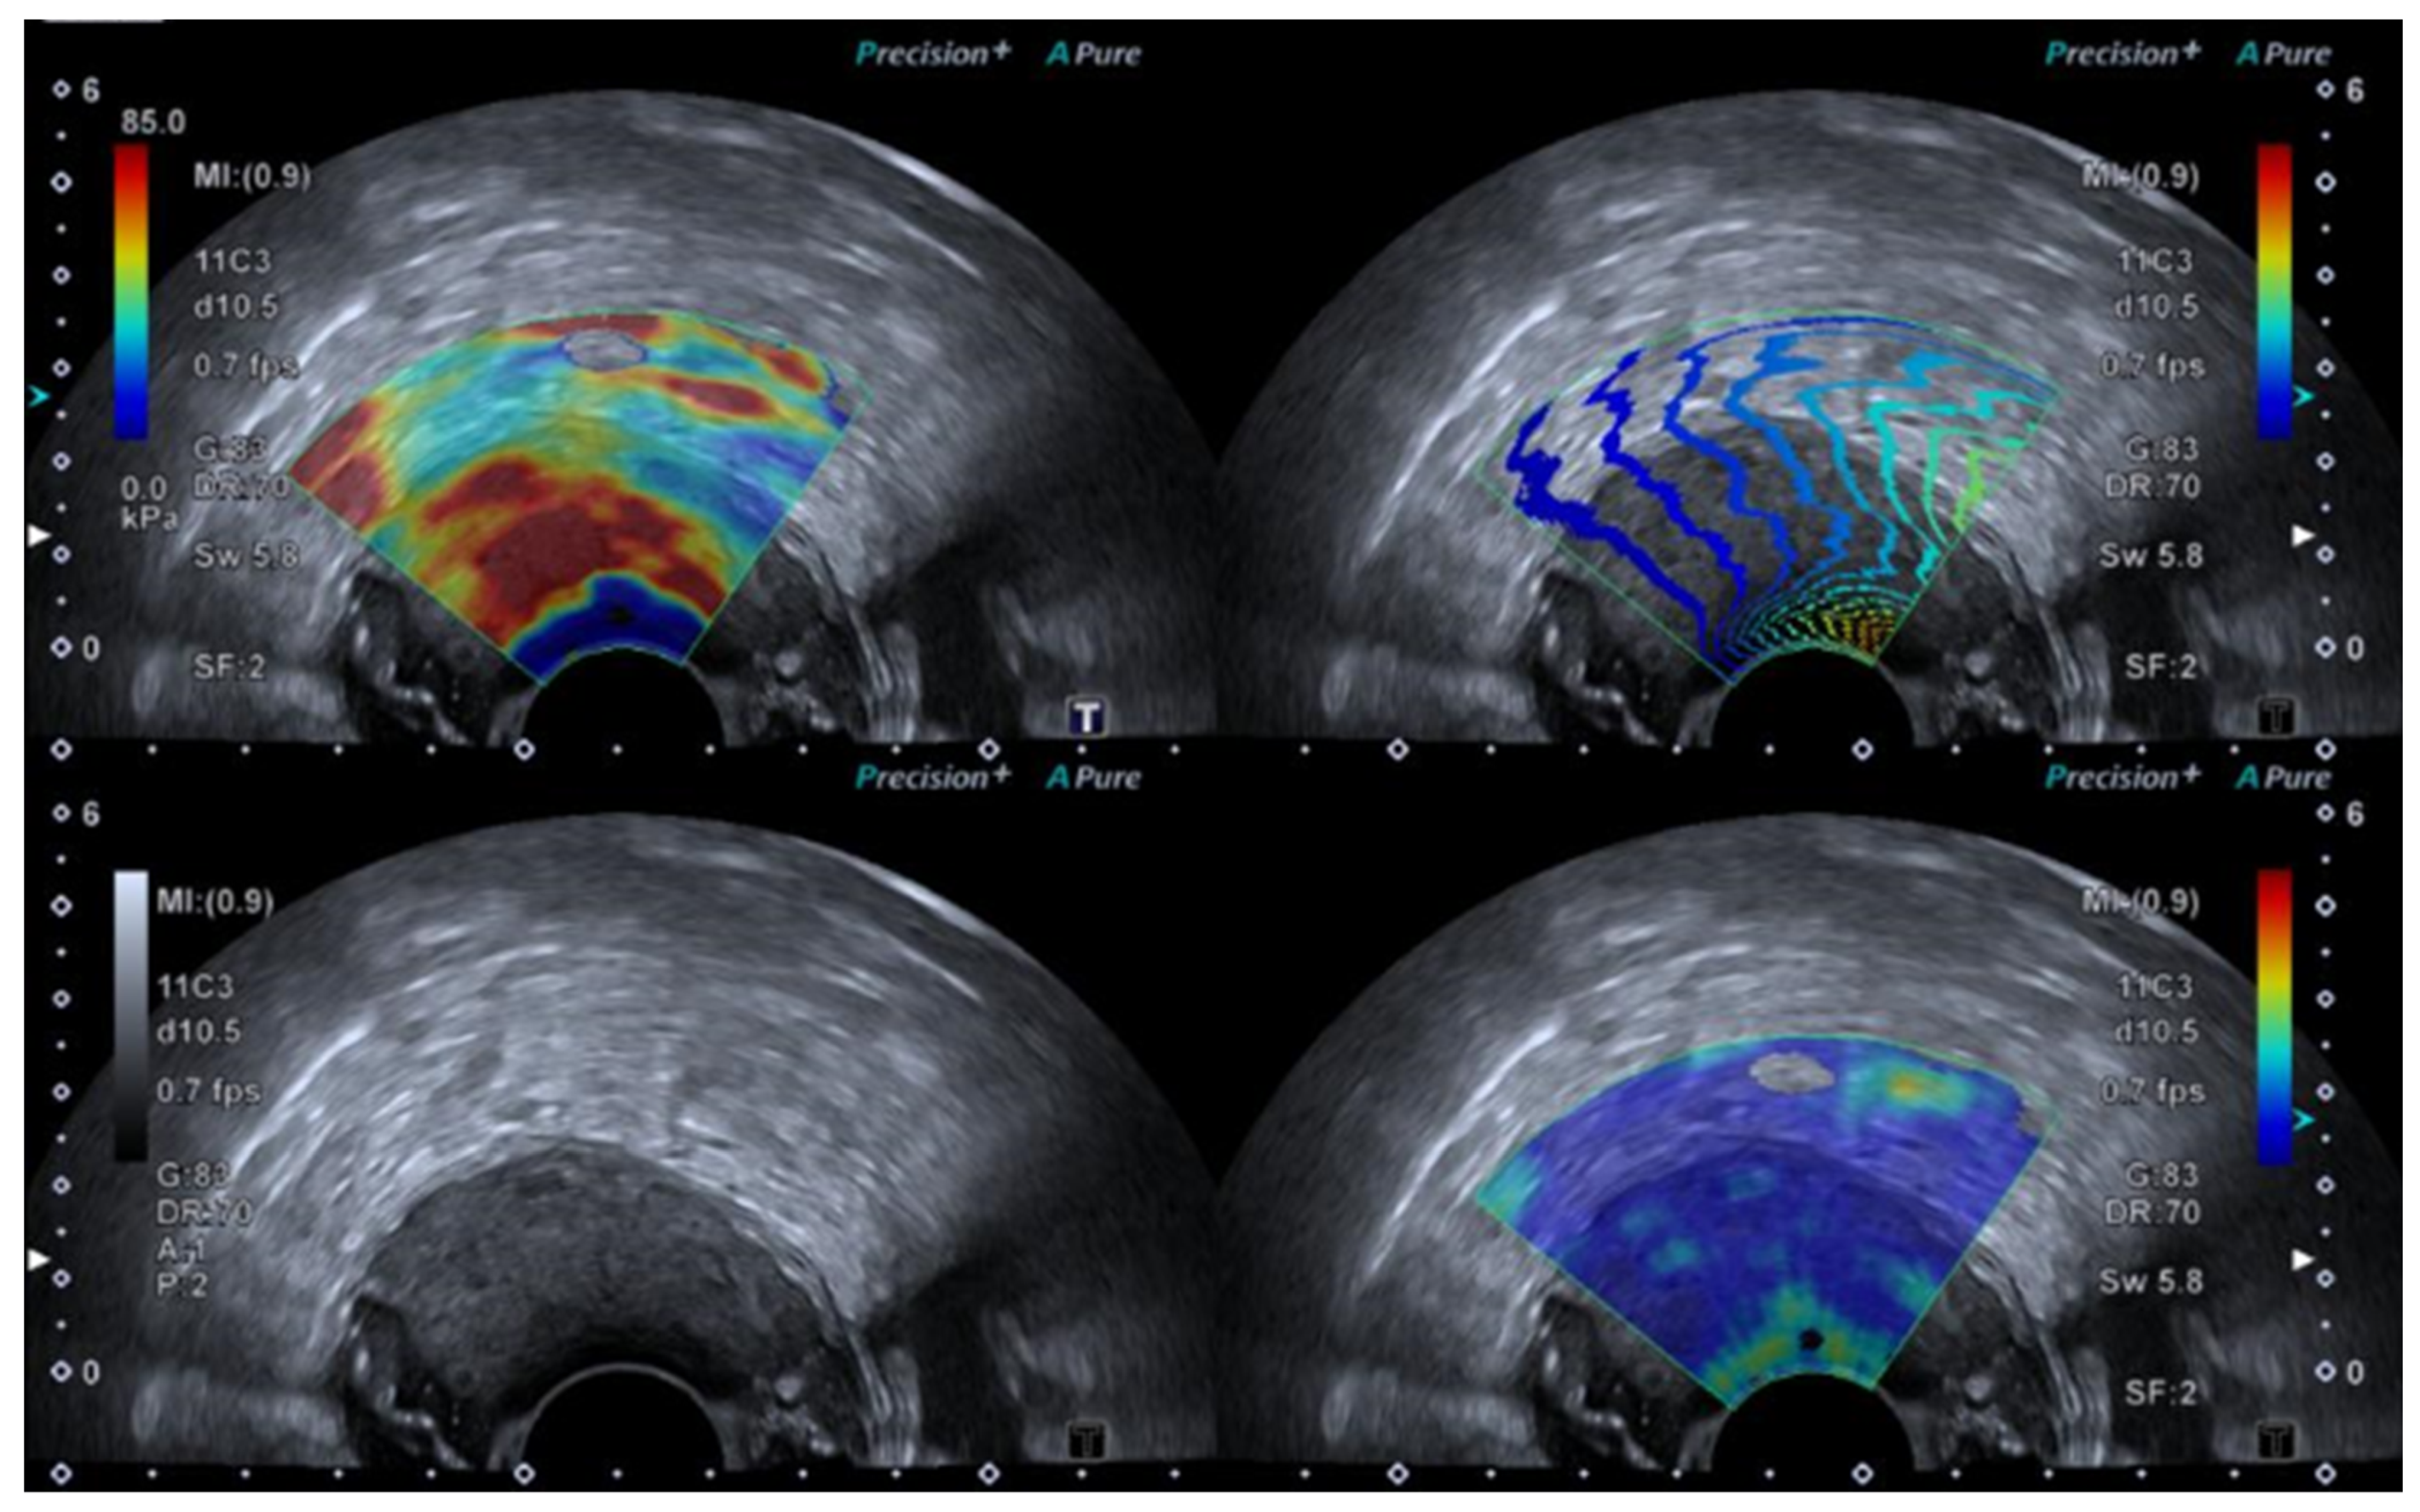

1.4.1. Strain or Compression Elastography

1.4.2. Shear Wave Elastography

2.4. Elastography—Change in Tumour Stiffness Caused by Malignant Transformation